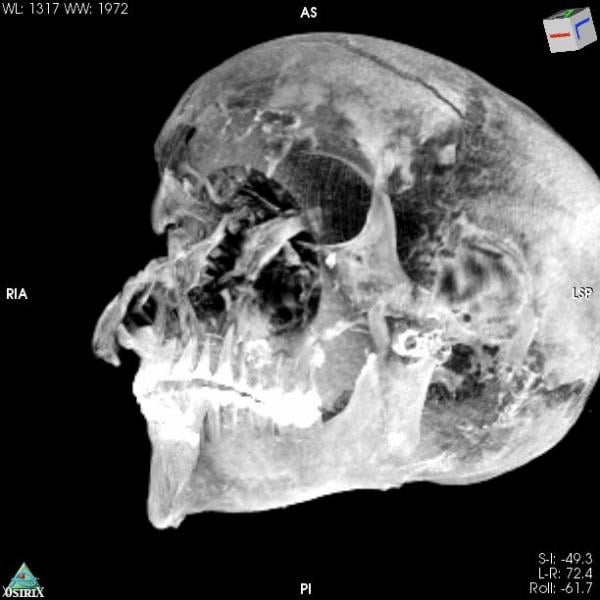

But computed tomography (CT) scans of the mummified remains of Seqenenre revealed new details about his head injuries, including previously undetected lesions that embalmers had skillfully concealed.

The authors of the new paper offer a novel interpretation of the events before and after the king's death based on the computer-processed X-ray images: Seqenenre had indeed been captured on the battlefield, but his hands had been tied behind his back, preventing him from defending against the attack.

For example, the CT scans, combined with other evidence, suggest the execution had been carried out by multiple attackers, which the scientists confirmed by studying five different Hyksos weapons that matched the king's wounds.

The CT study also determined that Seqenenre was about 40 when he died, based on the detailed morphology revealed in the images, providing the most precise estimate to date.

In addition, the CT study revealed important details about the mummification of Seqenenre's body. For instance, the embalmers used a sophisticated method to hide the king's head wounds under a layer of embalming material that functioned similarly to the fillers used in modern plastic surgery. This would imply that mummification took place in a real mummification laboratory rather than in a poorly equipped place, as previously interpreted.